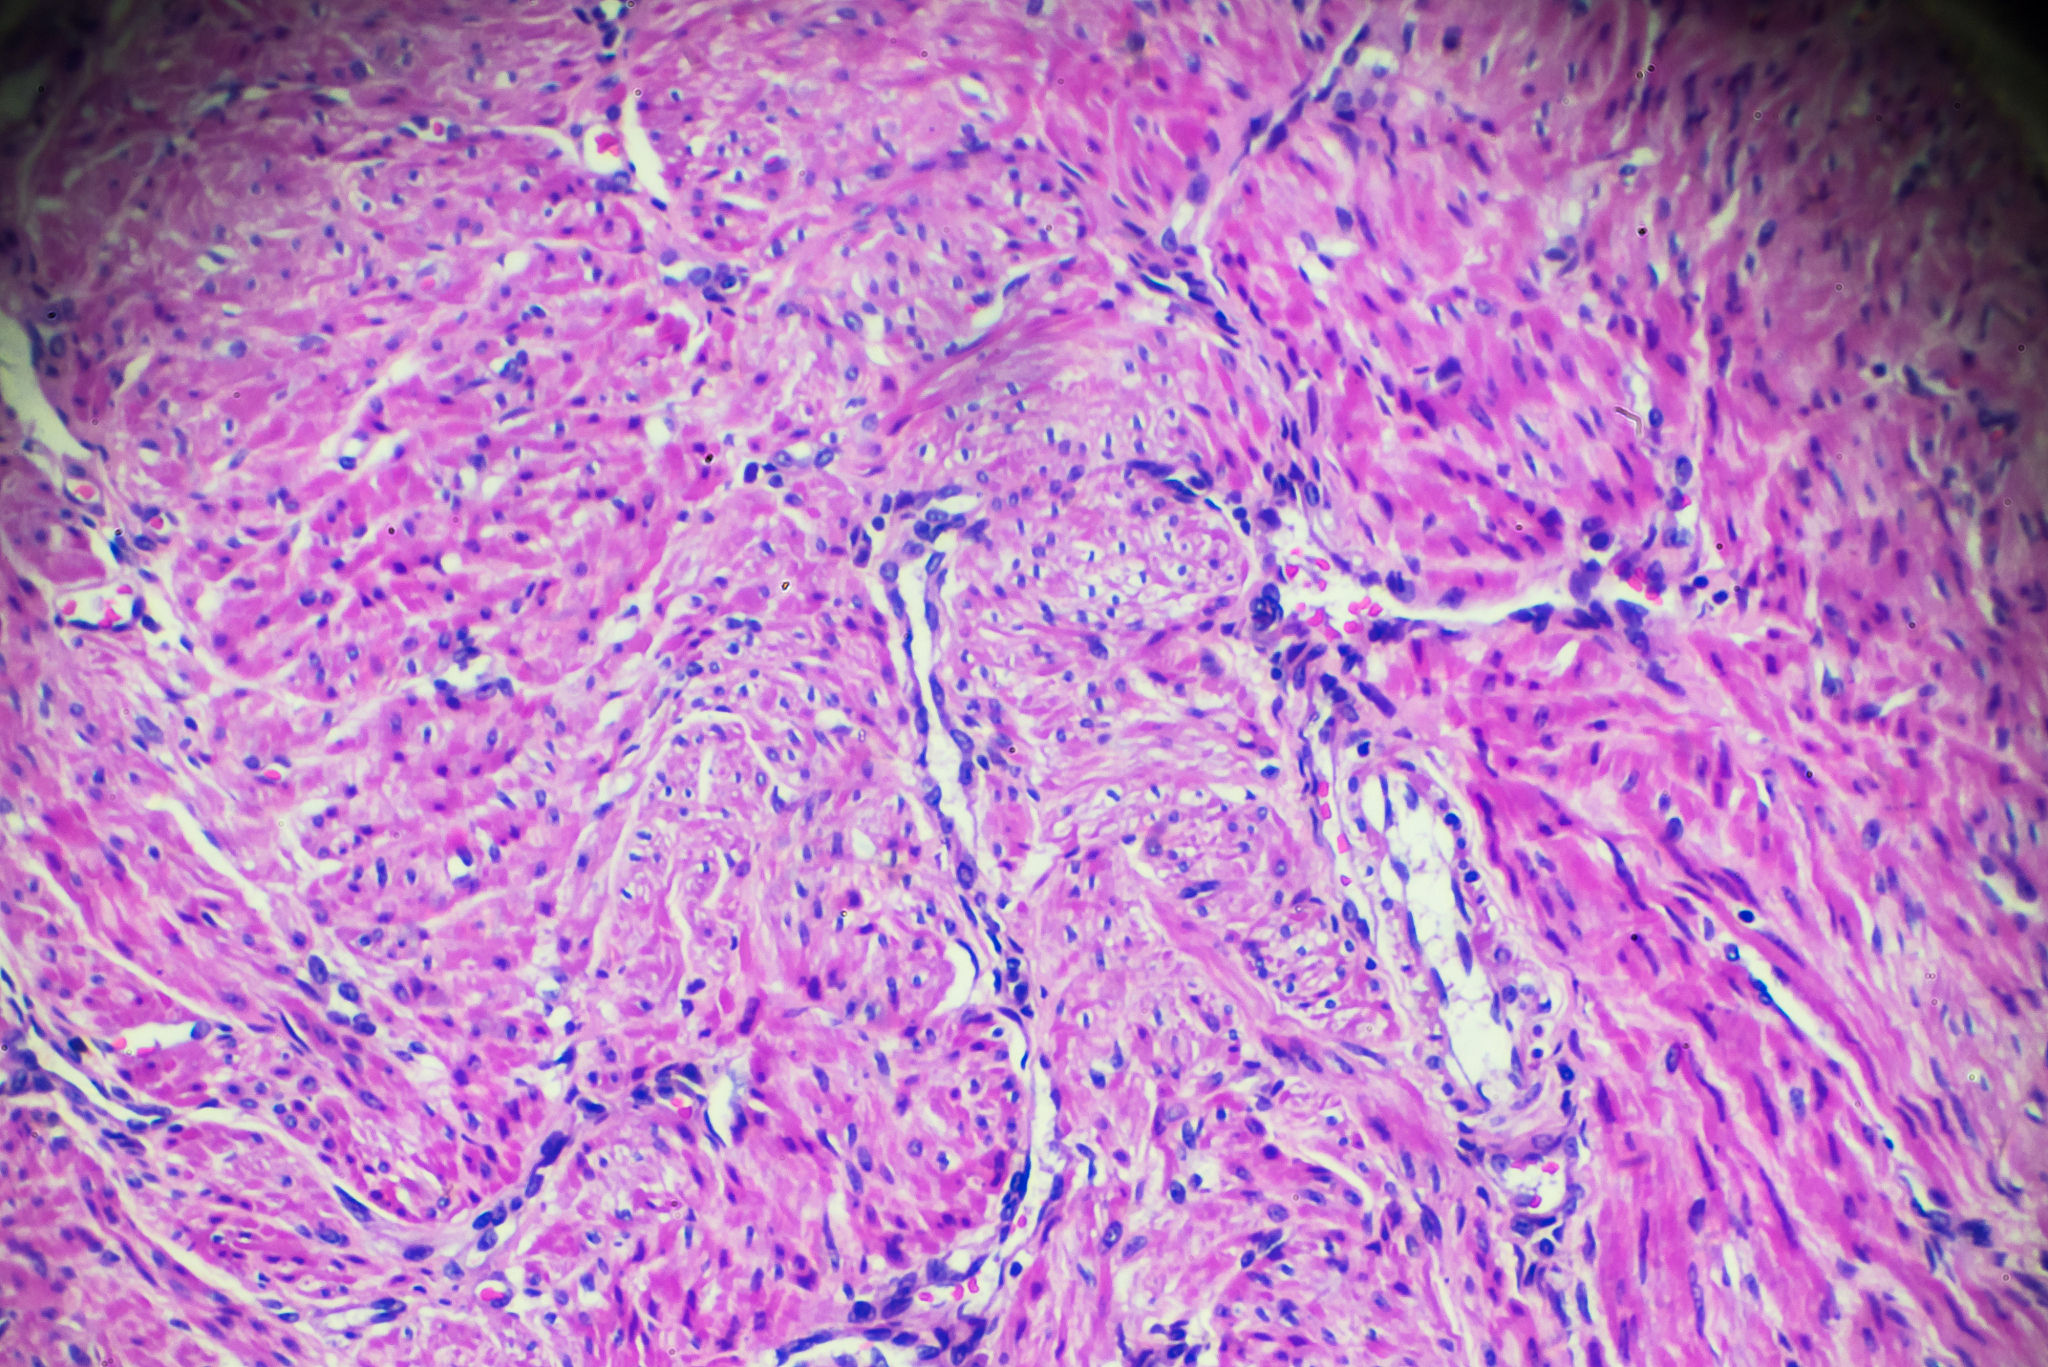

早期子宫内膜癌的需要腹主动脉淋巴结活检的包括以下哪几种情况A、乳头状浆液性腺癌B、子宫内膜样腺癌G3C、肌层浸润212D、灶累及宫腔面积超过50或有峡部累及

B、子宫内膜样腺癌G3 C、肌层浸润21/2 D、灶累及宫腔面积超过50%或有峡部累及